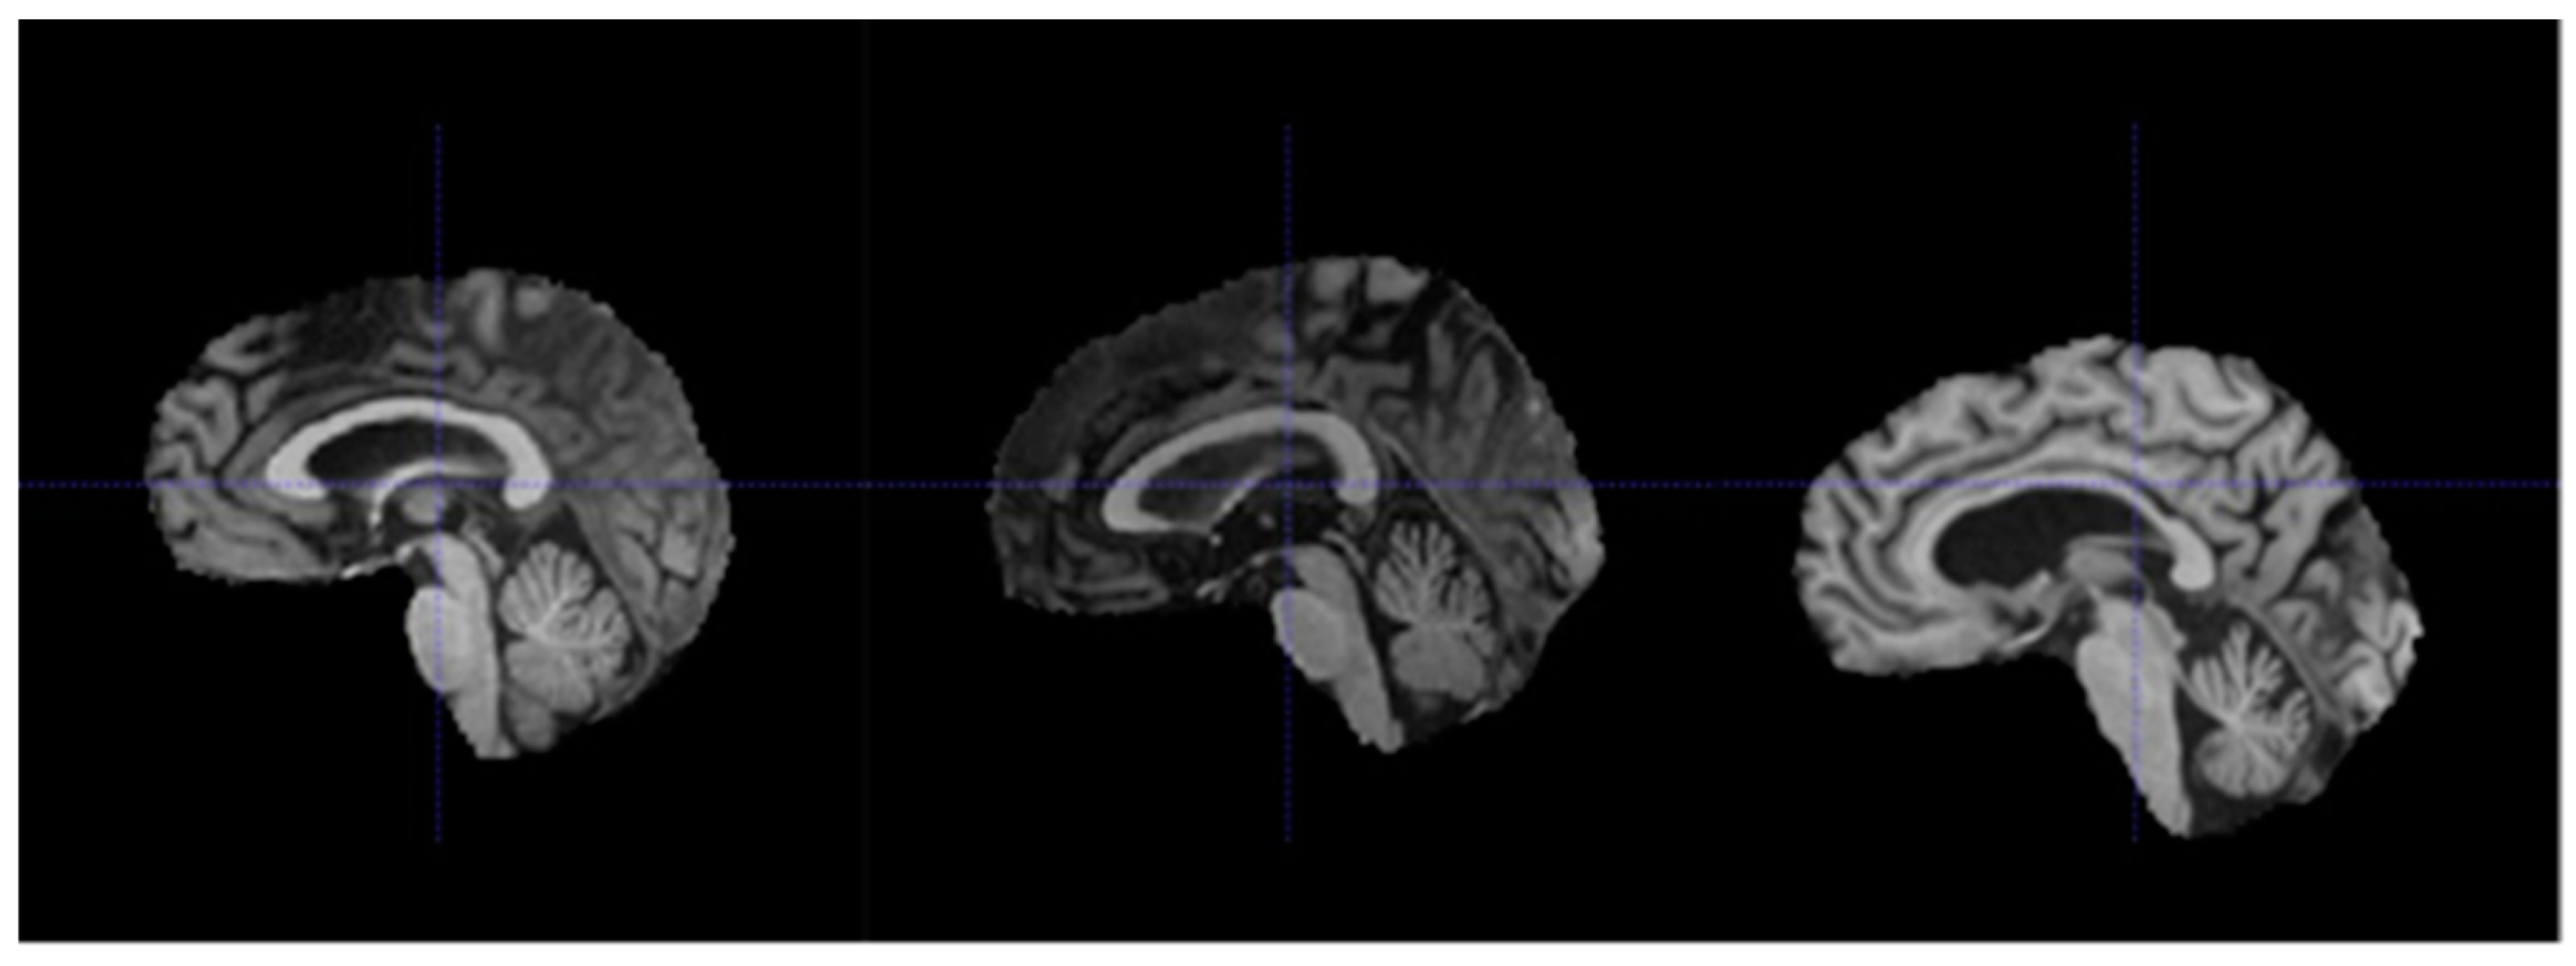

Generally speaking, each affine transformation matrix (and its inverse) represents the series of transformations required to map each voxel in the volume to a standardized reference space within the scanner [40]. In the HarP dataset, there were 15 subjects with different affine transformation matrices from the rest. One possible explanation is that for these 15 subjects, their MRI scans were taken using a tilted scan angle to obtain oblique scans [37]. Oblique scans are usually used to reduce noise caused by artifacts in the path of the magnetic field, such as air and water within the head of each subject. The use of oblique scans in these 15 subjects meant that even though registration was performed for these subjects, their MRI volumes may still not be as well aligned as those of the other 115 subjects [37]. This was further supported by our observations shown in Figure 5, in which the brain was situated lower in a MRI volume associated with a different affine transformation matrix.

Figure 5.

Sagittal views from subjects 067_S_1253 (left), 094_S_1293 (middle), and 023_S_0604 (right). Subject 023_S_0604 had a different affine matrix from the other two subjects.

In order to ensure that majority of the brain MRI volumes were well aligned and properly registered, these 15 subjects and their volumes were removed from the dataset. Therefore, the final data consists of the MRI volumes and hippocampus masks of 115 subjects. The next step of pre-processing performed was field inhomogeneity correction, also known as bias field correction. During the acquisition of an MRI scan, the magnetic field weakens as it encounters brain tissue, thereby causing inconsistencies in the intensities through the volumes (even for the same tissue types) [37]. These inconsistencies can make it difficult for the models to accurately detect the boundaries of different tissue types. Therefore, the N4ITK algorithm was used to perform field inhomogeneity correction for all volumes in the dataset [41] as shown in Figure 6 below.